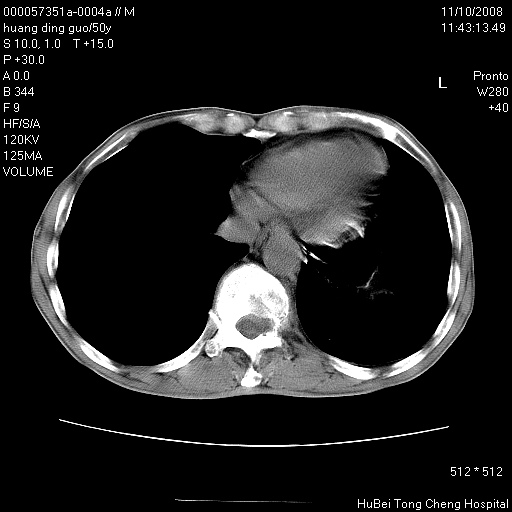

患者 男,50岁。左侧腰背部疼痛3月余,伴消瘦。平素健康,无传染病史。

胸部ct轴位平扫(层厚10mm,螺距1.5,重建间隔10mm),图像如下:

左肺下叶背段有一厚壁空洞,外壁呈锯齿状伴毛刺改变。空洞相邻胸膜有牵拉改变。左肺下叶血管支气管束不规则增粗,小叶间隔增厚。胸椎骨质破坏。考虑左肺下叶周围型肺癌伴左肺下叶癌性淋巴管炎、胸椎转移。

支持:左肺周围型肺癌伴癌性淋巴管炎\\胸椎转移瘤,不除外肺泡癌。(椎体破坏伴椎弓破坏)

左肺下叶背段有一厚壁空洞,内壁不规则,外壁呈锯齿状伴毛刺改变。空洞相邻胸膜有牵拉改变。周围呈絮状炎性改变,左肺下叶血管支气管束不规则增粗,小叶间隔增厚。胸椎骨质破坏。考虑左肺下叶周围型肺癌伴左肺下叶阻塞性肺炎、胸椎转移。